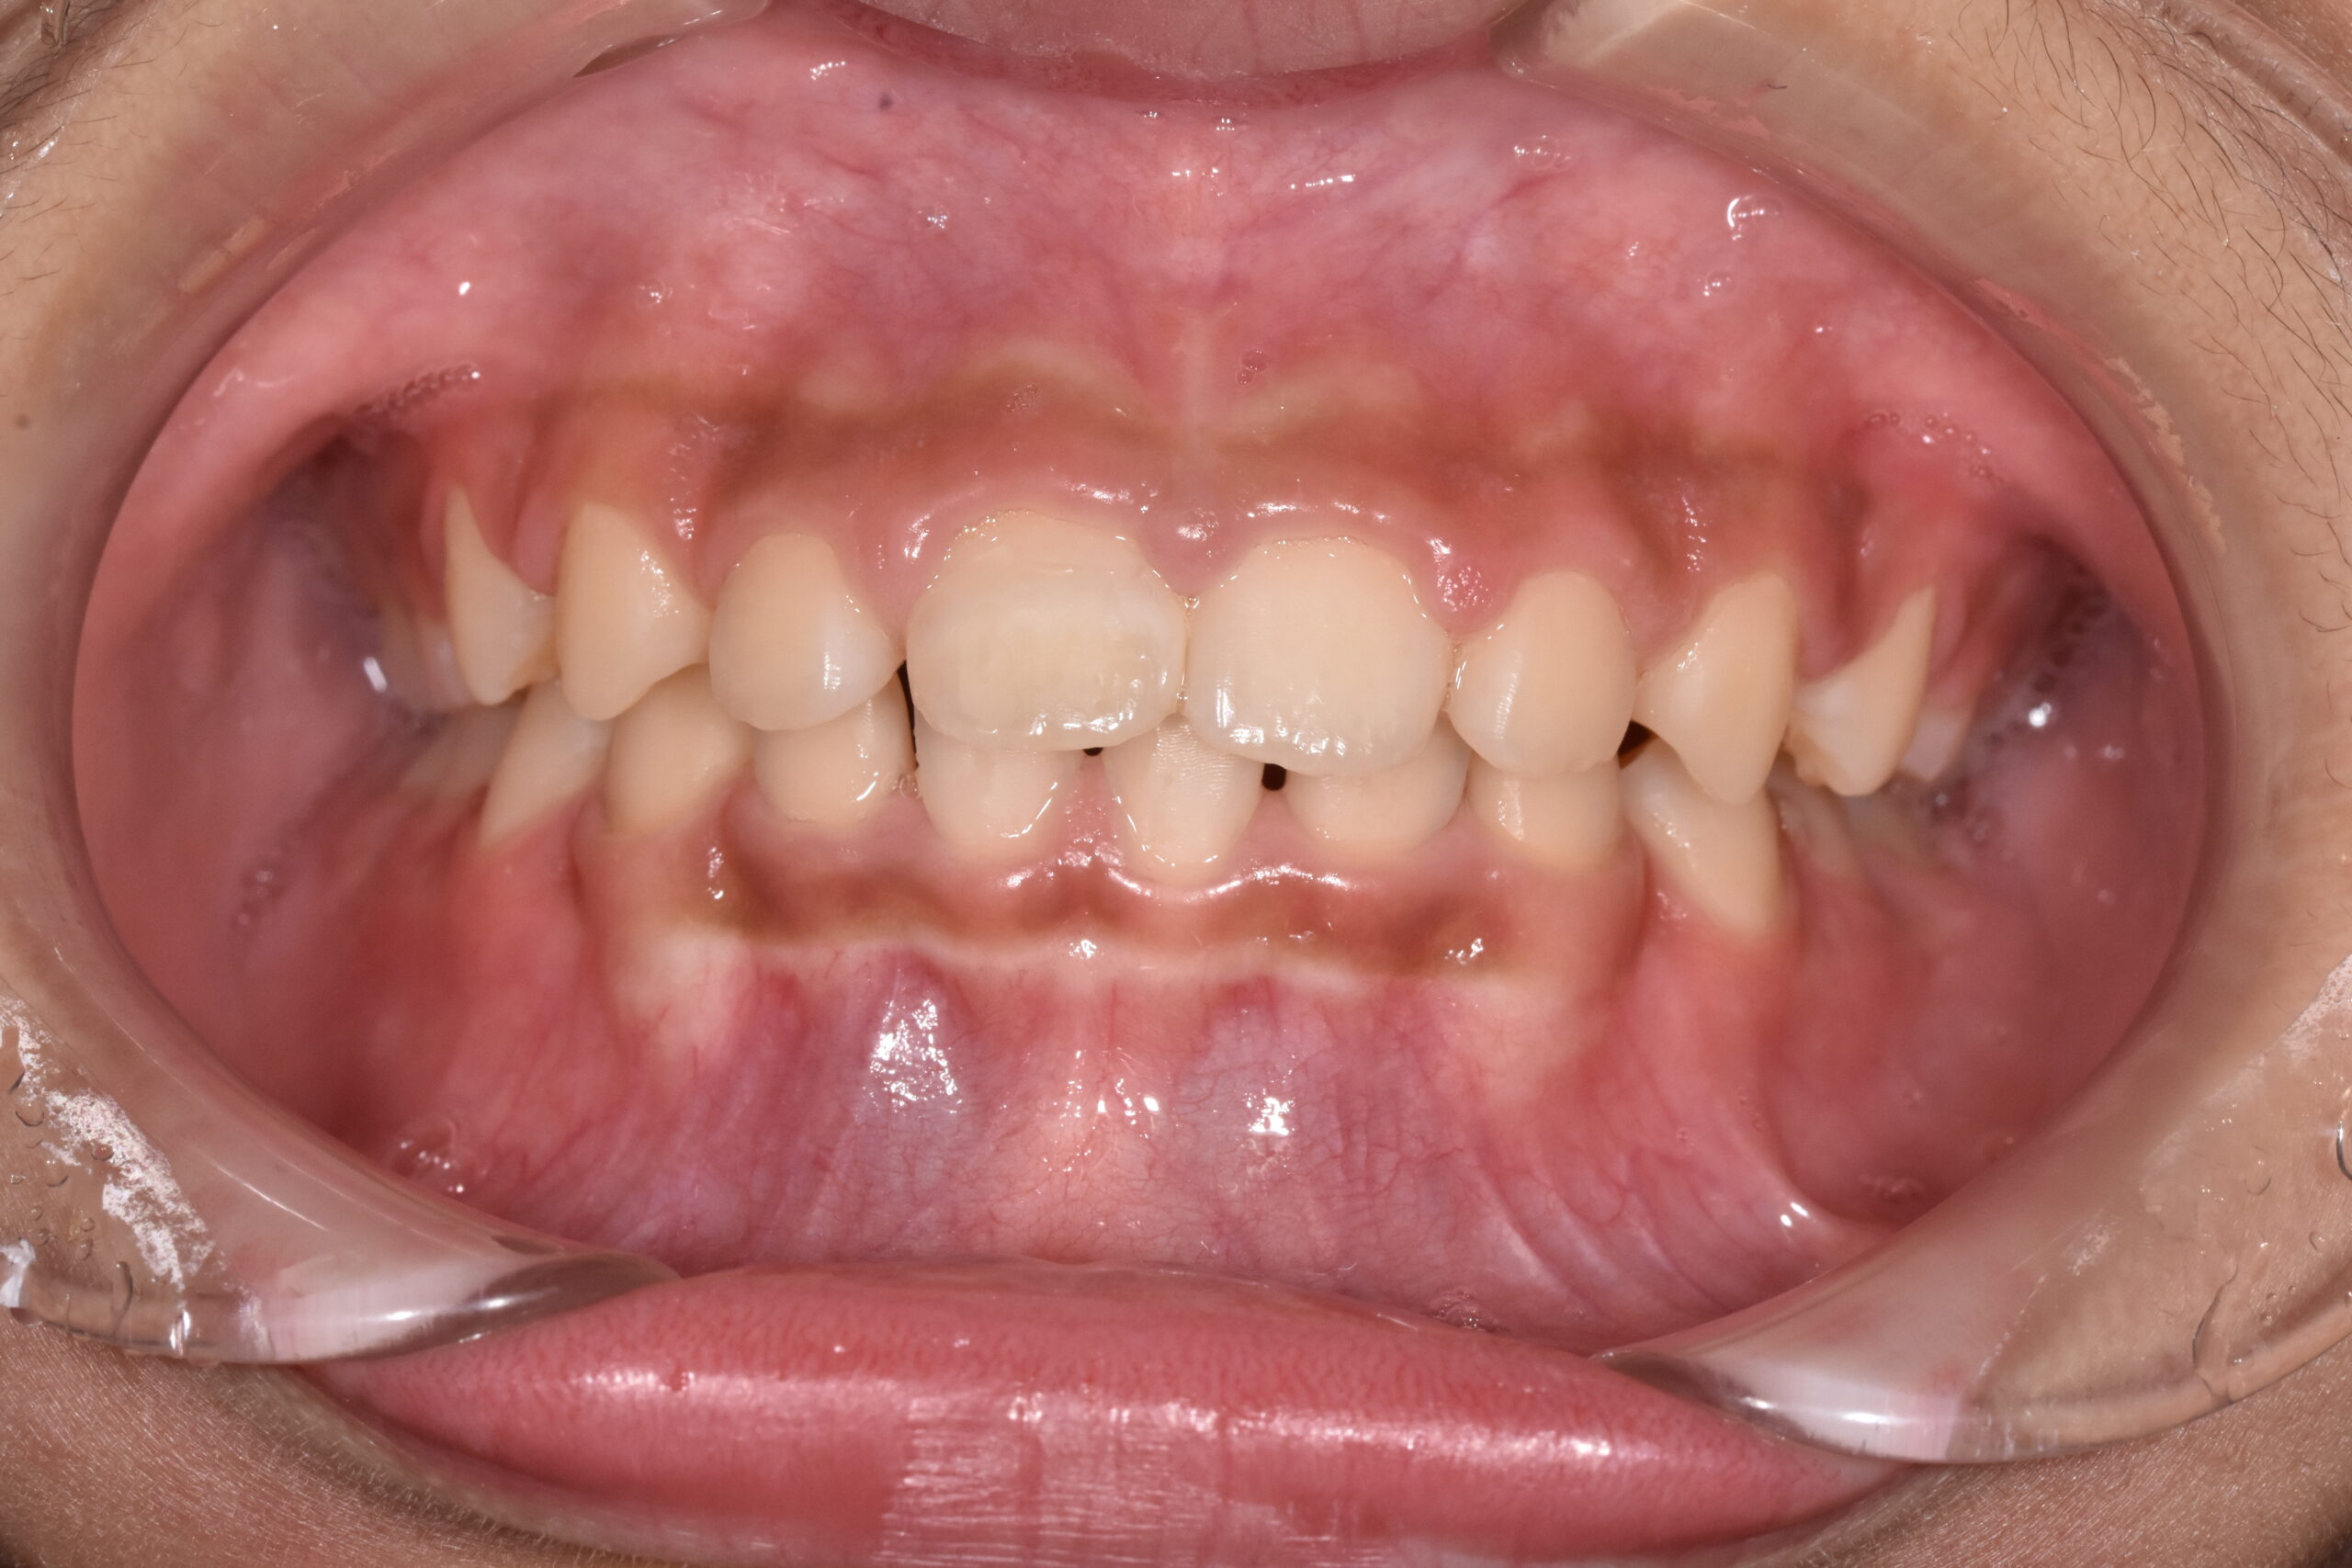

治療後

成長を利用した1期治療にて、マウスピース型装置や矯正装置を用い、歯並びと口元のバランスの改善を行いました

治療のポイント:

・成長期を活かし、口元の突出感を改善

・歯並びだけでなく、横顔(Eライン)にも配慮

・将来的な抜歯や本格矯正の負担軽減を目指した治療

・必要に応じて2期治療へ移行できるよう設計